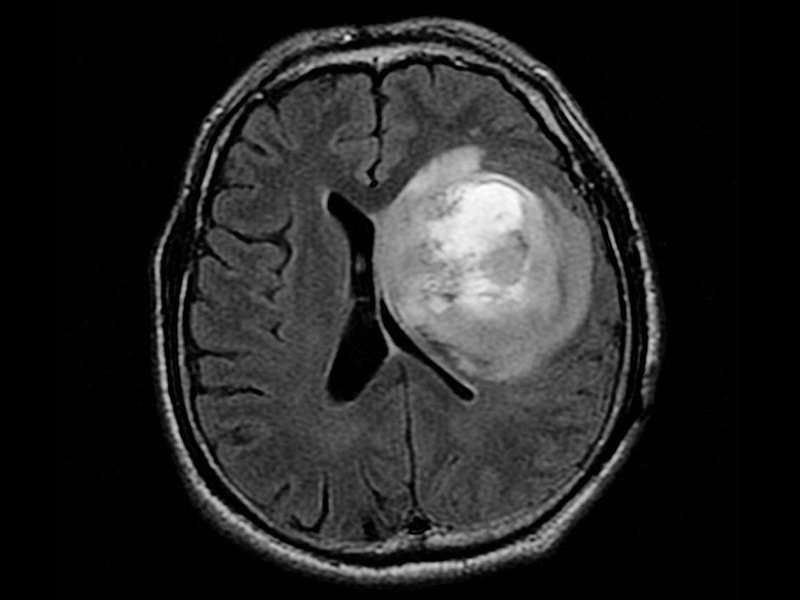

胶质瘤是指起源于神经胶质细胞的肿瘤,是常见的原发性颅内肿瘤,高级别胶质瘤的治疗以手术切除肿瘤为主,结合放疗、化疗等综合治疗方法。手术可以...

胶质瘤是成人较常见的原发性脑瘤。治疗方法取决于肿瘤的组织学、分子亚型和分级以及临床因素,如患者特征和肿瘤的手术可行性。患者所说的良性胶质...

神经胶质瘤 是在中枢神经系统的神经胶质细胞中形成的脑癌或脑肿瘤。胶质细胞是围绕并支持神经细胞的那些。一些脑癌起源于身体其他部位,而神经胶质...